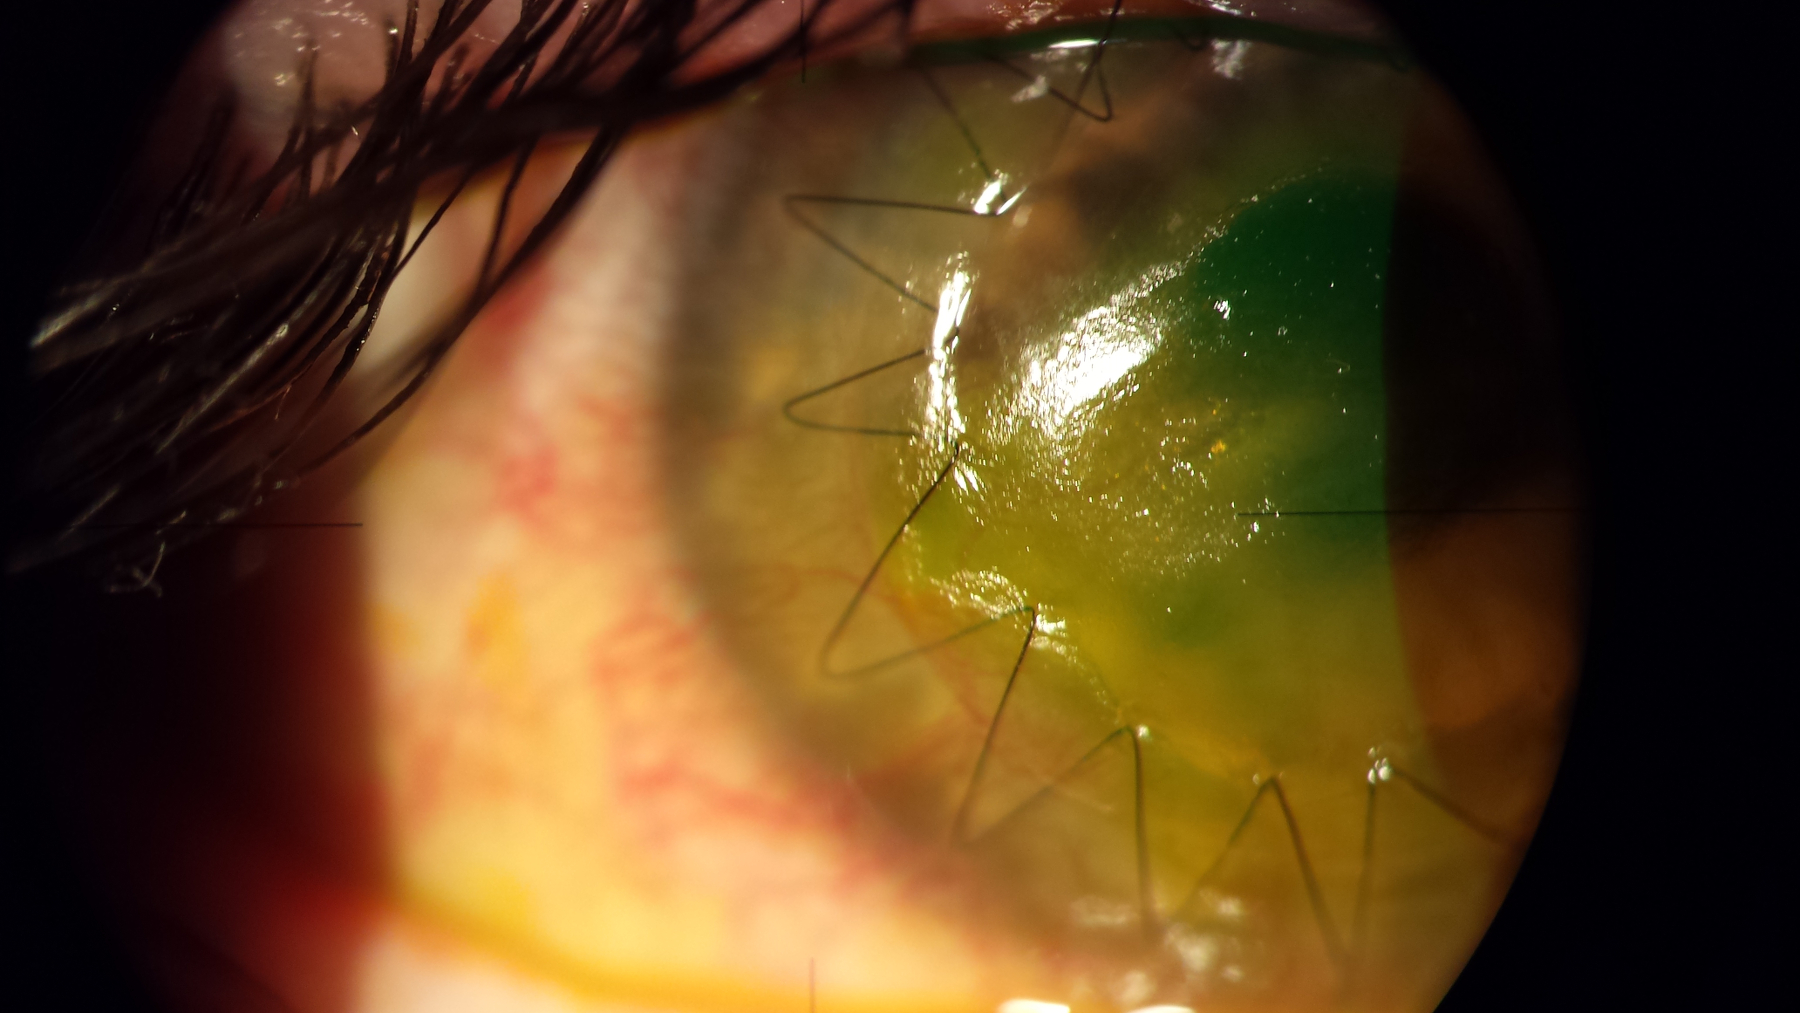

tod:16 mmhg bod: cornea trasparente lembo endoteliale ben posizionato (vedi foto cornea)

fod: nella norma L'esame OCT ha confermato lo spessore ultrasottile del lembo trapiantato (vedi OCT cornea)

I lembi ultrasottili e regolari permettono una più rapida e completa ripresa visiva e riducono la possibilità di rigetto corneale endoteliale.